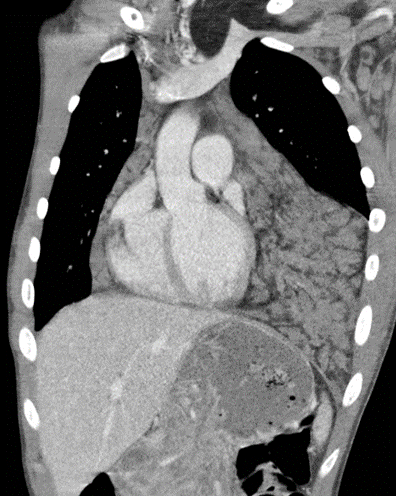

56 year-old man with sudden onset chest pain & shortness of breath… presented by Drs. Maxwell Cretcher, Gurion Lantz, and Dr. Cristina Fuss from @OHSUsurgery & OHSU Radiology. thoracicrad.org/assets/index/2…